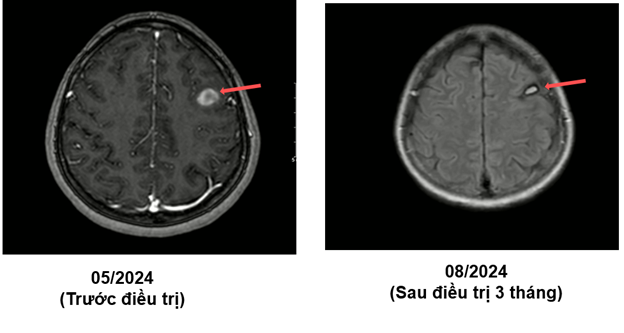

MRI sọ não sau điều trị:

Ct ngực sau điều trị:

Theo dõi định kỳ bằng lâm sàng, chụp CT ngực và MRI sọ não sau 3 tháng, 6 tháng và 15 tháng cho thấy:

- Tổn thương phổi và não giảm kích thước rõ rệt.

- Không xuất hiện tổn thương di căn mới.

- Tình trạng toàn thân ổn định, chất lượng sống được cải thiện.